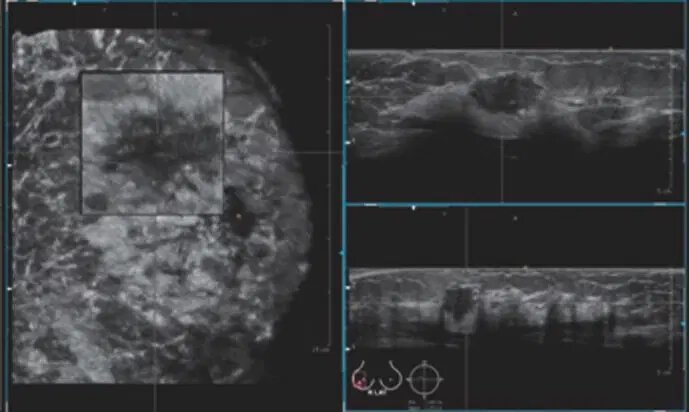

۲۰۰۹

سیستم سونوگرافی بسیار پیشرفته و اسکنر حجم پستان؛ که تصاویر حجمی با وضوح بالا را از پستان به دست میآورد. این سیستم برای استفاده در زنانی با بافت متراکم پستان، امکان تجسم نمای آناتومیک کرونی پستان را فراهم میکند.